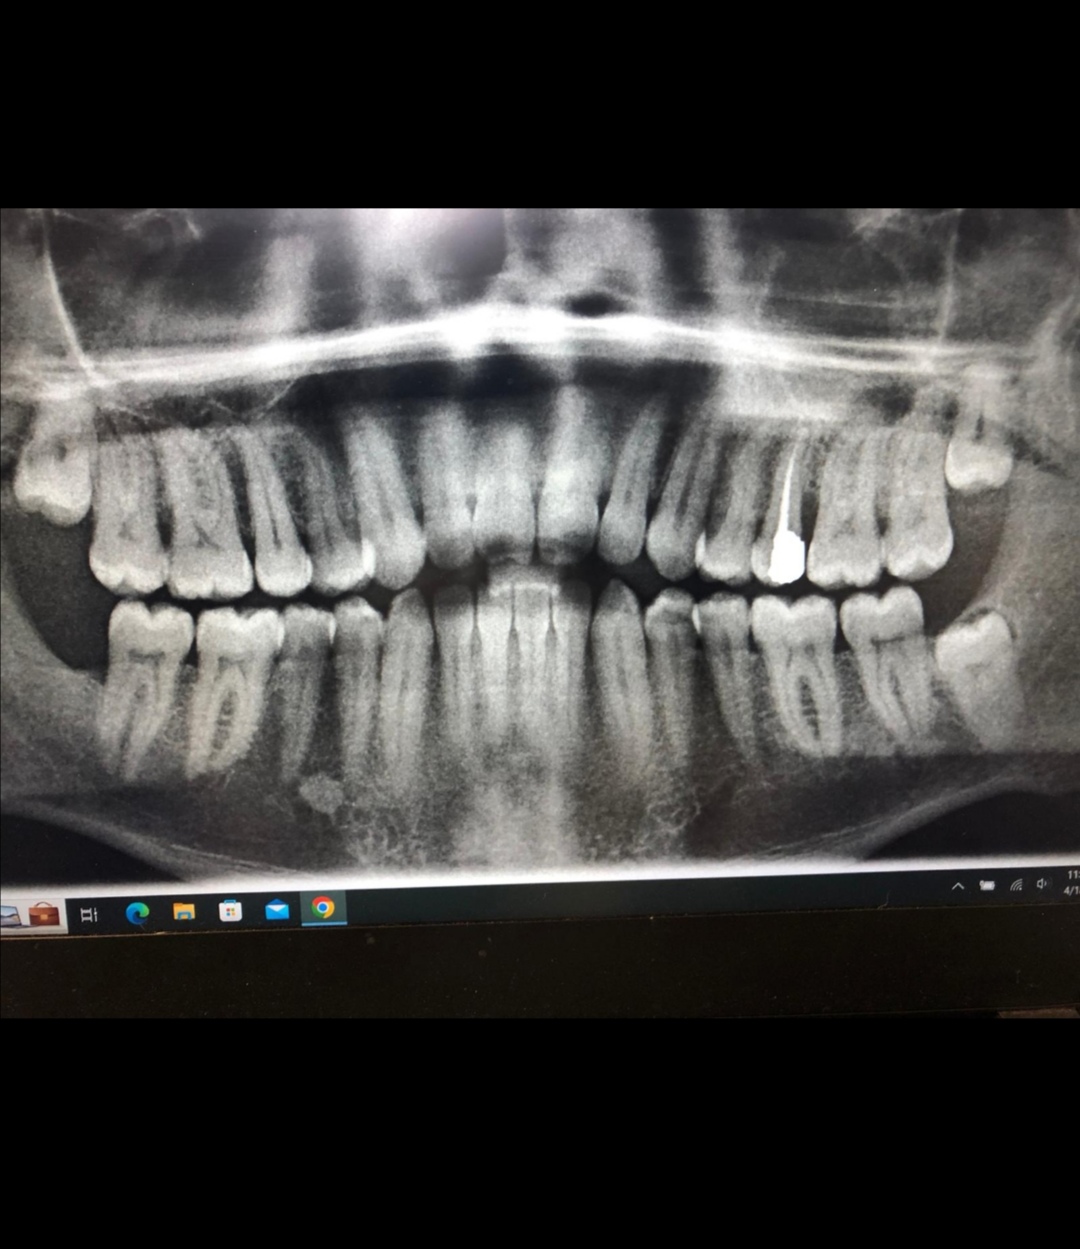

معرفة المشكلة في صور الاسنان